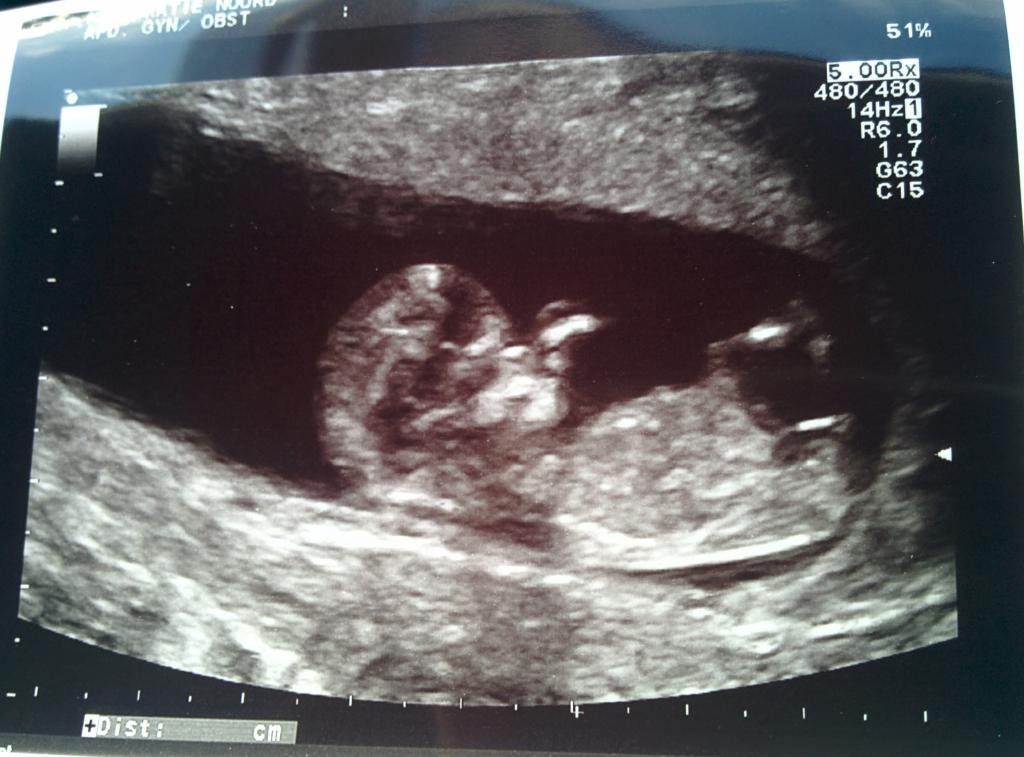

I have no clue if the nub is visible and where in my 11 week 4 day scan. Could anyone help me out? And if you see the nub, could you tell me where it is and whether it points to girl or boy? I would be very grateful for your help!

Attachment 23701Attachment 23702